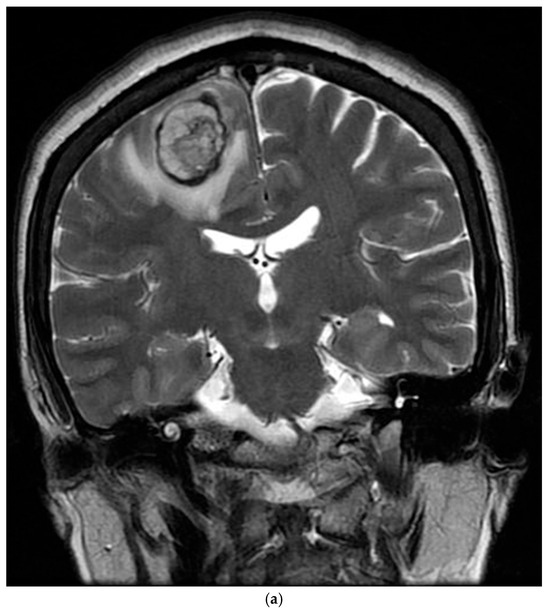

The patient’s postoperative period was uneventful, and she was discharged and subsequently administered chemotherapy. However, three months later, the patient was readmitted with left-sided hemiparesis. Brain MRI revealed a 25 mm T2-high signal and T1-low signal intensity mass with perilesional edema and faint peripheral enhancement in the posterior portion of the right superior frontal gyrus (Figure 6). Stereotaxic biopsy of the brain mass confirmed metastasis from the primary lung tumor. The metastatic brain tumor with hemorrhage was surgically removed, and the patient was started on chemotherapy and radiotherapy.

Figure 6.

Three-months postoperative coronal (a) T2 and (b) enhanced T1 images revealed a hemorrhagic rim-enhancing mass with perilesional edema in the right frontal lobe.